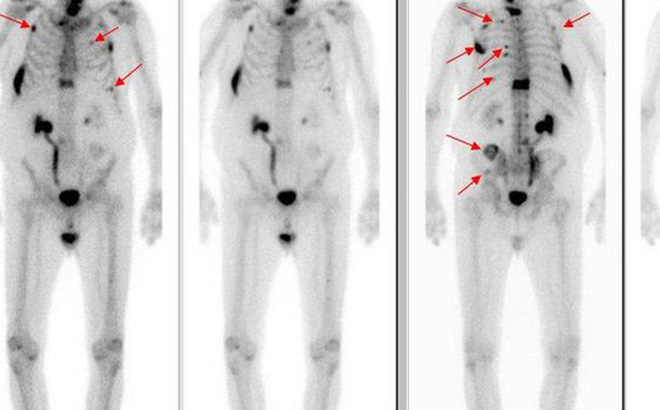

+ Di căn lên não: Có trên 30% bệnh nhân ung thư phổi bị di căn lên não. Đây là biến chứng nguy hiểm có thể gây tử vong nhanh chóng cho người. Hiện nay để kiểm soát các khối u di căn não thường có thể phẫu thuật lấy bỏ u (trường hợp u đơn độc, vị trí có thể mổ được), hoặc xạ trị gia tốc, hoặc xạ phẫu bằng dao gamma quay (an toàn và hiệu quả đối với những khối u nhỏ hơn 3cm và có ít hơn 3 u).

+ Di căn xương: Đây cũng là một biến chứng nguy hiểm của bệnh ung thư phổi. Bệnh nhân ung thư phổi đã di căn xương tiên lượng điều trị rất dè dặt, vì bệnh đã ở giai đoạn muộn. Ung thư phổi ở giai đoạn muộn đã lây lan đến xương, có thể gây ra đau xương, có nguy cơ gãy xương. Điều trị cho bệnh nhân lúc này chủ yếu là điều trị giảm triệu chứng, bệnh nhân đau thì dùng thuốc giảm đau, điều trị bảo tồn xương…